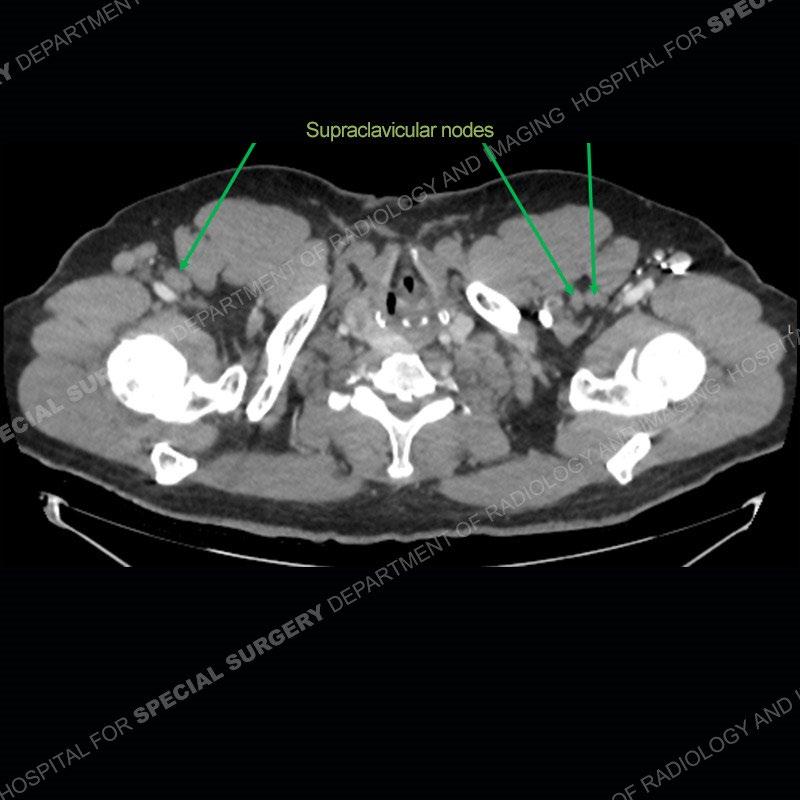

The chest radiographs demonstrate a leftward deviation of the trachea. CT images demonstrate a large, somewhat heterogeneous mass of the thyroid that extends outside the confines of the thyroid tissue. There is a subtle, enhancing soft tissue mass of the proximal right humerus. Slightly prominent mediastinal lymph nodes are present with additionally, multiple supraclavicular lymph nodes.

Although not strictly a part of the evaluation of an “incidental” thyroid lesion, evaluation of the adjacent lymph nodes and bony structures can also be quite important. In this case, there is an enhancing mass of the right humerus. This is very subtle and can only really be recognized by evaluating the density of the bone. Typicaly marrow will have a fatty density or nearly fluid density. As the density, as in this case, approaches soft tissue an infiltrative process must be entertained. Thyroid mets are markedly vascular accounting for the areas of enhancement of the humeral mass. The mediastinal and supraclavicular lymph nodes although not individually enlarged, should raise suspicion of an underlying inflammatory/neoplastic process.